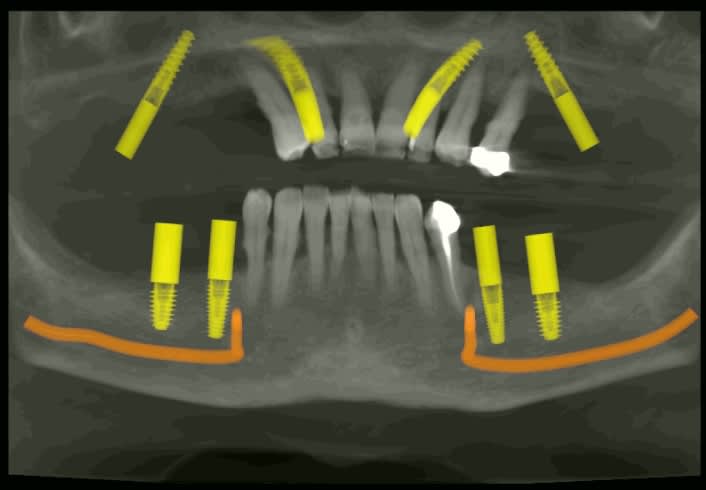

Le cone beam prévu : all on 4 et 4 implants en bas qui seront posé dans 3 semaines.

4g05g0zkqb9uamhomemvsdunbwuq - Eugenol

Vykhhmf4es3hera2t6to30davd7b - Eugenol

H0mho0nweh14081abwcqkpuwecah - Eugenol

Tcs2qgbo81hf6lsnsvo4zas78sej - Eugenol